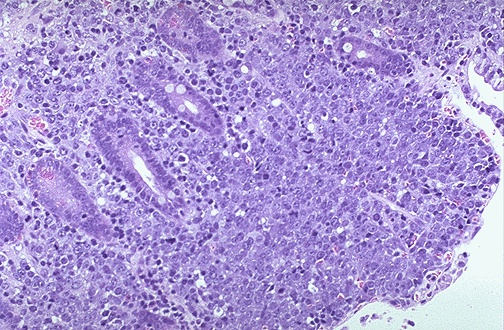

The large blue non-Hodgkin lymphoma cells can be seen infiltrating through the mucosa.